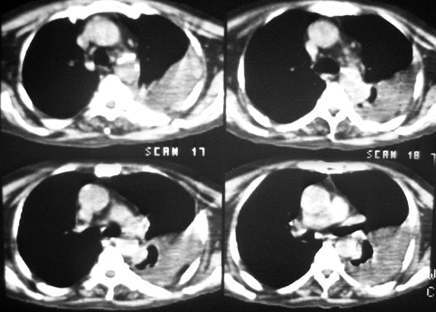

长年偏瘫卧床的病人,73岁,男。最近不能自理,饮食差,知觉不敏感,bp:140/80。脑ct是脑动脉硬化的表现,陈旧多发脑梗死。听诊左肺呼吸音低。行胸部ct扫描发现左侧大量胸腔积液,左侧肋骨虫蚀样破坏,请给予会诊一下:是否转移性病变还是其他?谢谢!

左侧后肋骨及椎弓骨质破坏,考虑转移瘤.降主动脉旁见一软组织块影,肿瘤与压迫之不张肺组织不能鉴别,建议增强扫描.

考虑;左侧周围性肺癌侵犯胸膜并肋骨转移.

考虑肋骨骨质破坏,病变肋骨皮质不连续,呈融骨样改变,不象骨质损伤后的修复样改变,未见到明显骨痂显示.软组织肿胀不明显,所以不太支持感染性破坏改变.

肋骨骨质破坏!!中下部纵隔窗传上来看看!该不会有肺癌吧?纵隔内有淋巴结影。

左肺上叶尖后段实变、体积缩小,支气管开口后方似有一肿块,与胸壁、主动脉分界不清,局部肋骨呈混合型破坏,考虑肺癌肋骨、胸膜转移。

左侧包裹性胸腔积液,未见到明确的肿块影,纵隔窗伪影严重,纵隔可见到淋巴结(位于主动脉弓下)左侧肋骨病变是否与患者长年卧床有关